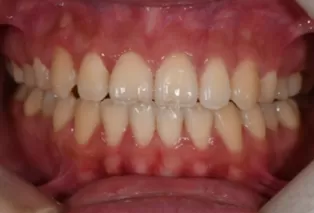

Photos intra-orales après traitement